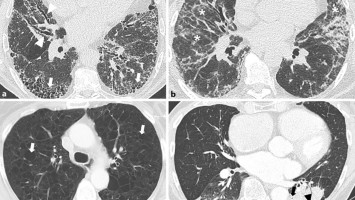

Rheuma und interstitielle Lungenerkrankung hängen oft zusammen!

Eine interstitielle Lungenerkrankung (ILD) kann als Folge einer rheumatischen Grunderkrankung auftreten, sie kann dieser aber auch vorausgehen. Bei der Abklärung sollte man daher beides im Blick haben.